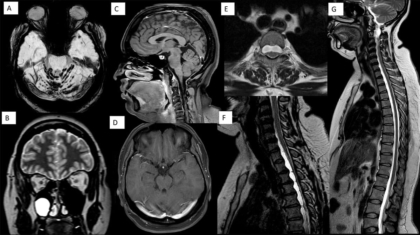

A 43-year-old lady presented with chronic headache of 15 years. Headache aggravated on prolonged standing and walking.